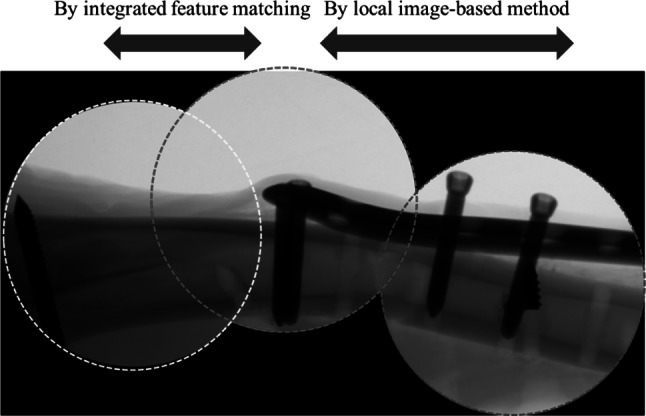

Figure 7 shows the stitching outcome of the proposed method of the X-ray image of the caprine tibia with a fixation plate. In alignment with Fig. 4, the stitching was only successful using the proposed method. Three images and their boundaries in each image are indicated by the dotted colored circles. Although the overlap region was sufficiently large between the first and second input image, it was significantly narrower between the second and the third input image. Therefore, while the first stitching was successfully conducted for several methods, the second stitching failed in all of the conventional methods. Conversely, by adopting a local image-based estimation, the proposed method could stitch the images even if the overlap region was extremely limited. Typically, when the overlap region is limited, stitching with detected features is impossible, since a sufficient number of reliably matched features in a limited region is not found. However, in the proposed method, the limitation of conventional X-ray image stitching caused by the very narrow overlap region can be overcome by heterogeneous stitching using homographic evaluation, depending on the area of the overlap.

Fig. 7.

Heterogeneous stitching depending on the overlap region using the proposed method